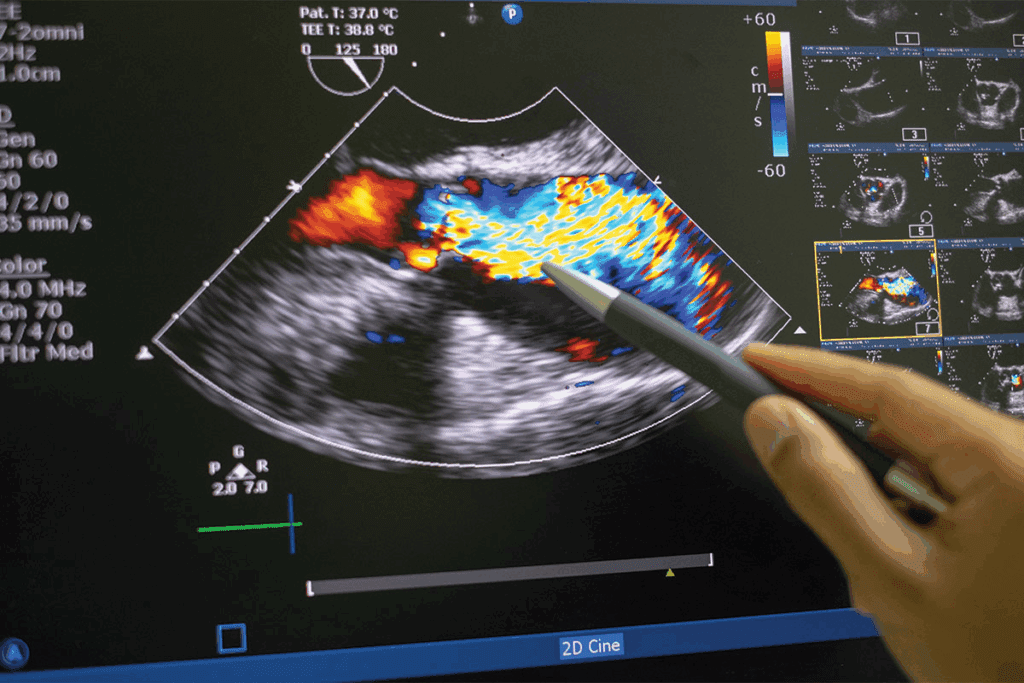

Diagnostic Methods: Ultrasound, MRI, and Clinical Evaluation